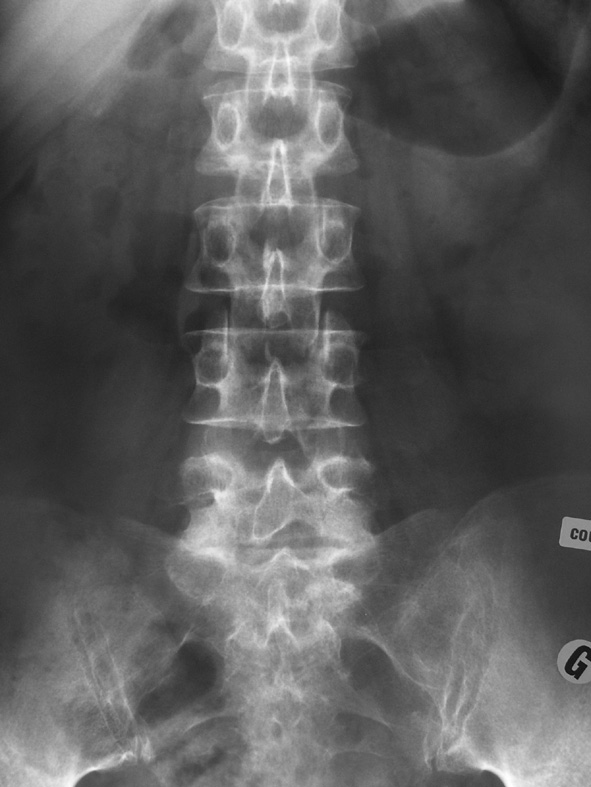

Monsieur B., quarante-quatre ans, professeur de mathématiques, sans antécédents, vient vous consulter pour une lombalgie irradiant dans le membre inférieur gauche. La douleur lombaire est apparue il y a quinze jours après un effort de soulèvement. Il s’agit d’une douleur lombaire basse, relativement supportable, irradiant à la face postéro-externe de la cuisse, à la face externe de la jambe et au dos du pied. La douleur est aggravée par les efforts, soulagée par le repos, impulsive à la toux.Son seul antécédent est une malposition urétérale opérée dans l’enfance. L’examen clinique montre un signe de Lasègue à gauche à 55°, une colonne lombaire enraidie et douloureuse à la palpation. Il n’y a pas d’anomalie à l’examen neurologique, pas de fièvre, pas d’altération de l’état général. Il vous apporte ses radiographies et son scanner qui explore L5S1 et L4L5 (clichés ci-dessous).

Décrivez l’image scanographique. Est-elle compatible avec le tableau clinique ?